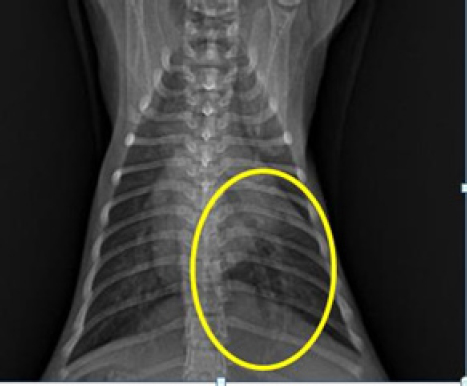

X-ray interpretation

The outcomes of the X-ray investigation revealed the occurrence of discoloration in the abdominal cavity, accompanied by a noticeable progression in opacity. This phenomenon is commonly attributed to the emergence of fluid in the abdominal cavity (Figs. 2 and 3).

Fig. 2. Thoracic radiograph of Hiro’s cat in a dorso ventral (DV) changes in vascular patterns with dilatation of the pulmonary arteries and veins caudals.

The X-ray findings reveal a change in opacity in a section of the abdominal cavity, indicating an increase in radiopacity and the presence of ascites, or fluid buildup. Ultrasound imaging of the same area reveals anechoic regions between organs, which is a sign of fluid accumulation (Prajapati et al., 2022). Ascites are a symptomatic condition that occurs when fluid, both transudate and exudate, leaks into the space between the peritoneum and visceral layer of the abdominal cavity (Tilley et al., 2021). This is often a result of congestive heart failure or impaired venous flow and may cause cats to experience lethargy, abdominal distension, discomfort upon palpation, anorexia, vomiting, weight gain, scrotal or prepuce edema, and pain while lying down. Hypoalbuminemia, or low levels of albumin in the blood, is a contributing factor to ascites, as it reduces plasma osmotic pressure and increases vascular permeability, leading to fluid leakage from blood vessels into the abdominal cavity (Restijono et al., 2020).

Following changes occur in the caudal pulmonary arteries and veins or vascular patterns observed in the dorsoventral view of the X-ray position, specifically alterations in size. The pulmonary veins and arteries caudalis exhibit dilation, resulting in a vessel diameter larger than the IXth rib diameter, this is consistent with previous research, which states that enlargement of the left atrium and pulmonary veins is one of the symptoms of CHF in cats (Guglielmini and Diana, 2015; Bernes et al., 2020). The dilation of pulmonary arteries and veins is due to augmented pressure from systemic veins toward the right ventricle (Berry, 2010). The upsurge of pressure from systemic veins toward the right ventricle is caused by the improper blood circulation process in the right atrium and ventricle, leading to a small output of blood from the ventricles and the retention of blood in the heart chambers at the end of systole, which increases. This condition increases hydrostatic pressure, leading to the dilation of pulmonary arteries and veins (Triakoso, 2020). The high hydrostatic pressure causes fluid leakage from veins into pleural and peritoneal spaces, and potentially into pericardium and peripheral interstitial tissues. Ascites occur when fluid leakage surpasses the lymphatic system’s capacity (Tilley et al., 2021).